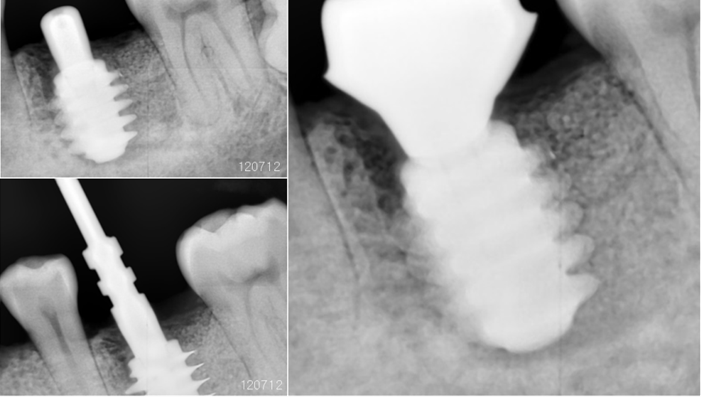

“AnyRidge with Root Membrane Technique shows

comparable long-term success rates to

conventional immediate implants. ”

Clinical case: Replacement of fractured central incisor (#11) with immediate implant

& Root Membrane Technique

- Courtesy of Dr. Miltiadis Mitsias, Greece -

Keywords

AnyRidge, Root Membrane Technique, retrospective study, long-term study, immediate implants, bone resorption, bone preservation, Dr. Miltiadis Mitsias,survival, success, maxillary anterior, single replacement

Products:

AnyRidge implant system, Root Membrane kit

Reference

The Root Membrane Technique: A retrospective clinical study with up to 10 years of follow-up./Implant Dent. 2018 Oct;27(5):564-574

https://www.ncbi.nlm.nih.gov/pubmed/30161062